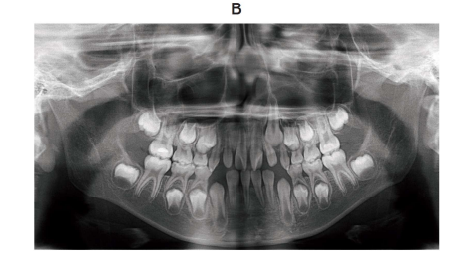

8 歳の女児。医科から歯科を受診するよう指示されて来院した。 1 か月後に骨髄

移植を予定しているという。下顎右側臼歯部に冷水痛がある。医科に対診したとこ

ろ観血的処置に関して問題ないとのことである。診察の結果、永久歯への交換の近

い歯と感染源になり得る歯の抜去を行うこととした。初診時の口腔内写真(別冊

No. 7A)とエックス線画像(別冊No. 7B)を別に示す。

抜歯部位はどれか。 1 つ選べ。

解答:d

解説:

う蝕があるのは↓

骨髄移植を控えているのなら感染源は絶ったほうがよい。感染源が全身に流れると危ない。右下6番は大事だしう蝕ではないので残す。

DEは10~11歳、Cは9歳~10歳頃に抜ける。

左下Eはレントゲン見ると齲蝕が歯髄まで広がっていて大きい。歯髄までひろがっていると感染の可能性が高いので抜歯。

交換間近の歯も抜くって問題文に書いてある。ということは前歯部は歯胚も見えているし交換間近でああるので抜歯。